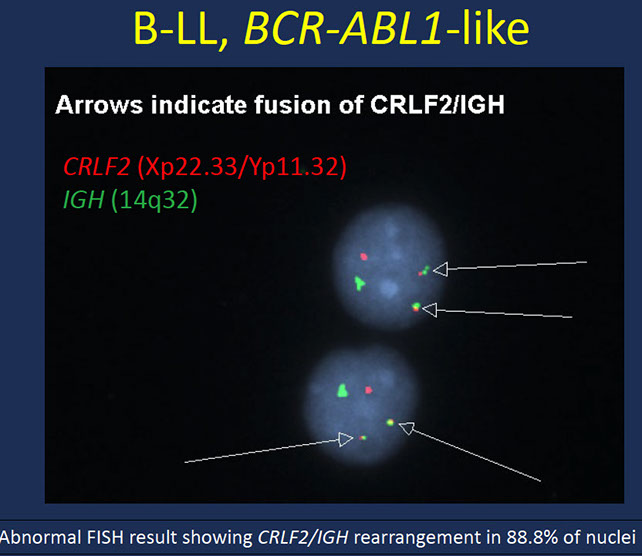

B-lymphoblastic leukemia/lymphoma, BCR-ABL1-like

Practical approach to identification

– Selecting an optimized screening approach and defining the appropriate population to screen is a challenge

• High index of suspicion

• If available, CRLF2 expression by flow

• Advanced applications

– Specific phenotype using small set of genes, FISH probes or molecular methodologies (LDA, RNA seq)

Incidence: relatively common (~20%)

– Higher in children with high risk ALL, adolescents and adults

– Down syndrome, high rate of CRLF2 translocations

– IGH/CRLF2 translocation common in Hispanic and Native American populations

• Clinical, morphologic and immunophenotypic features similar to other subtypes of B-LL

– Often present with higher WBC counts

– CRLF2 expression by flow distinctive

• Lacks the BCR-ABL1 fusion/Philadelphia chromosome, BUT

• Shows a gene expression profile that is very similar to B-LL with BCR-ABL1

• Because of the clinical importance of identifying these cases, added as a distinct WHO entity – 2017

• Overall poor prognosis

• High risk of poor response to therapy and relapse

Genes: Although heterogeneous, converge on activation of kinase signaling pathways

– JAK/STAT pathway

– ABL-class genes

– Increased signaling due to IKZF1, FGFR1, RAS

• Some of these translocations may be detected by routine cytogenetic analysis but others are cryptic

JAK/STAT pathway activation

– Cytokine receptor-like factor 2 (CRLF2)

• 50% of cases of Ph-like cases

• Majority due to P2RY8-CRLF2 and IGH-CRLF2

• Typically show high CRLF2 levels by flow cytometry

– JAK - Activating point mutations (30-50% of CRLF2-rearranged cases)

• JAK rearrangements (5-7%)

– Erythropoietin receptor (EPOR)

• 1-5% of cases

• Protein overexpression

ABL class abnormalities

– Typically results in fusion genes as a consequence of translocations/similar rearrangement

– e.g. ABL1, ABL2, CSF1R, PDGFRA, PDGFRB

– Create constitutive activation of tyrosine kinase signaling proteins